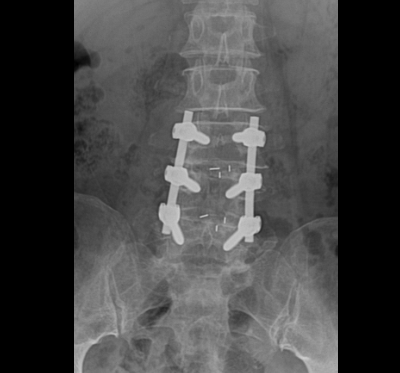

Qua thăm khám và các chỉ định cận lâm sàng cần thiết, bác sĩ Khoa Ngoại Chấn thương chỉnh hình chẩn đoán người bệnh bị thoát vị đĩa đệm L34, L45 gây hẹp nặng ống sống thắt lưng và chèn ép rễ thần kinh ngang mức. Bệnh nhân được chỉ định phẫu thuật cố định cột sống, giải ép thần kinh và hàn xương liên thân đốt L34, L45.

Ca phẫu thuật được tiến hành thuận lợi, sau phẫu thuật bệnh nhân hết triệu chứng đau nhức 2 chân và đã được hướng dẫn tập Phục hồi chức năng ngay sau mổ. Theo bác sĩ Nguyễn Mạnh Thuần – Khoa Ngoại chấn thương chỉnh hình, thoát vị đĩa đệm gây chèn ép rễ thần kinh, tủy sống thì phẫu thuật giải ép, ghép xương liên thân đốt và cố định cột sống là phẫu thuật triệt để và ổn định nhất cho người bệnh.